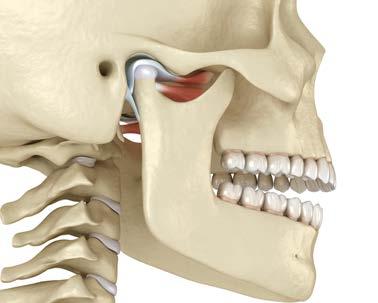

Dentista y Paciente 28 Calidad y dirección Fotoarte: Editorial Renascence | Fotografía: AdobeStock Diagnóstico Temprano y Tratamiento Interceptivo en la Disfunción de la Articulación Temporomandibular

La disfunción de la articulación tem poromandibular, es el resultado de la evolución combinada de factores que, durante el crecimiento y desa rrollo craneodentofacial, genera inestabilidad en la relación, posición y dinámicas funcionales de los ele mentos anatómicos que conforman el universo estomatognático; es por tanto necesario que un diagnóstico temprano y el adecuado tratamiento interceptivo, armonicen y estabilicen las relaciones de posición y función del bloque óseo dental, junto con las biomecánicas adecuadas del comple jo neuromuscular. La relación cén trica ideal requiere de una oclusión céntrica óptima en cada caso, tanto en el paciente en desarrollo como en el adulto. Los factores ambientales, sociales, psicológicos, sumados a las alteraciones del desarrollo por enfer medades o aspectos congénitos, así como los ocasionados por la acción de una odontología deficiente, son detonantes que a corto, mediano y largo plazo se reflejan en la salud arti cular y oclusal del paciente. Lo que confiere la importancia de realizar acciones preventivas y correctivas durante el crecimiento y desarrollo y de tratamientos de rehabilitación adecuados para el adulto centrado en la estabilidad de posición, dinámi ca y función en la articulación tem poromandibular y en una máxima

intercuspidación acorde a las bases apicales y a la correcta estabilidad de las cargas en la oclusión.

Discusión

Una detección temprana de altera ciones en el universo estomatogná tico, con la aplicación de maniobras adecuadas en base a un diagnóstico integral, evitará complicaciones en el desarrollo y funcionamiento adecuado a nivel articular y oclusal (Figura 1).

Por otro lado, la articulación tempo romandibular, está conformada por:

• Un eje.

• Una posición espacial.

• Características anatómicas indivi duales.

172. Diciembre 2022

33

Diagnóstico temprano y tratamiento interceptivo

25

26 27 28 29

• Centro de rotación y de traslación.

• Límites biofuncionales.

• Centros de comando neuronal.

• Potencial de acción y reacción así como la capacidad de movimiento y retorno. Todo contenido en una capsula articular, amortiguada por un menisco, trabajando en armonía con su contraeje en los movimien tos mandibulares.